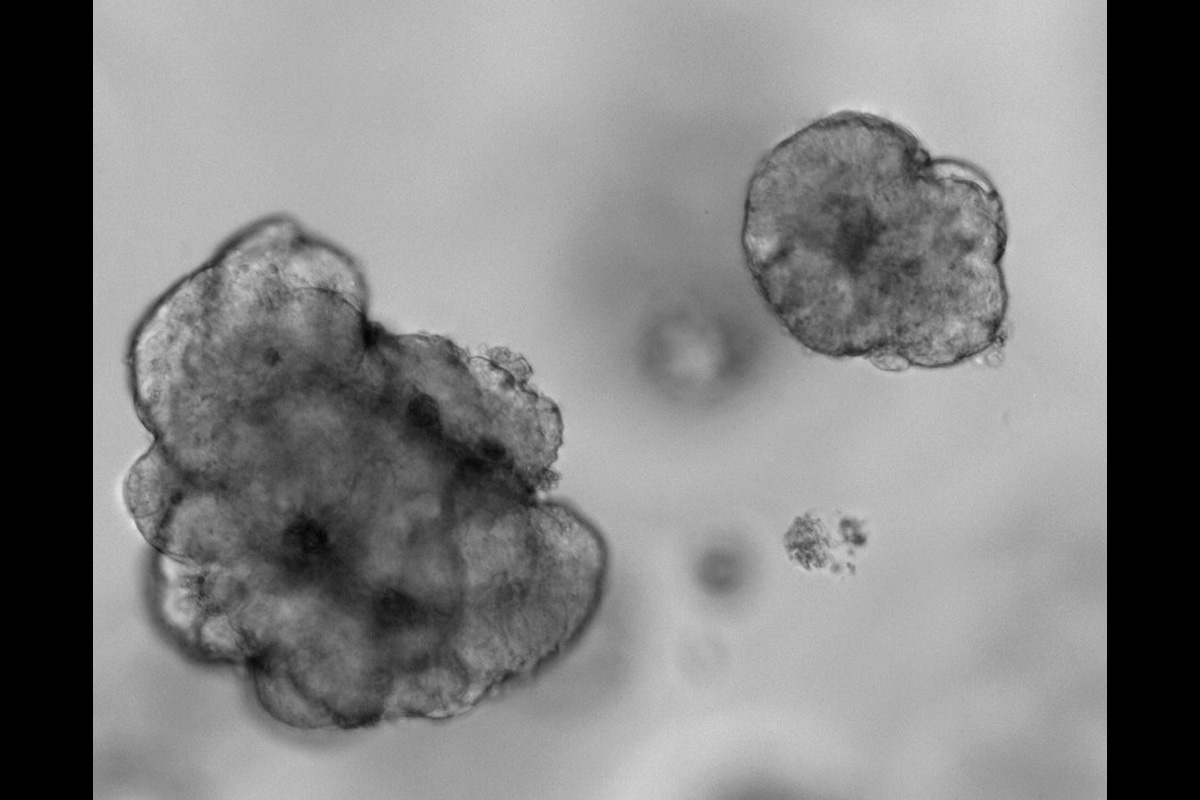

Tumoroids were established from rectal cancer biopsies